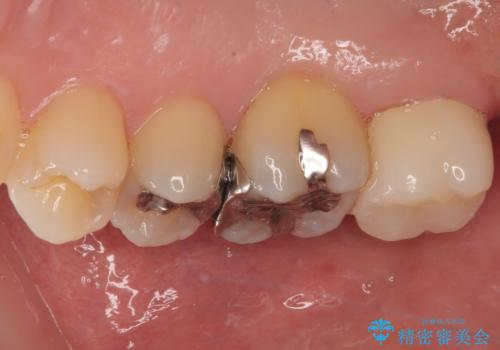

- 元々むし歯があったものの、処置が困難とのことでしたが、矯正治療を終えたので処置をしたいとのことで来院された患者様です。

左右ともに最後臼歯が頬側に顕著に突出しており、むし歯になってしまったことが想像されました。

矯正治療により処置が可能な位置に歯が移動したため、オールセラミッククラウンにて補綴治療を行うこととしました。

歯列が移動したとはいえ、左右ともに後方傾斜しており、むし歯の除去、形成(形を整える)、型取りの全てが非常に困難な処置となりました。